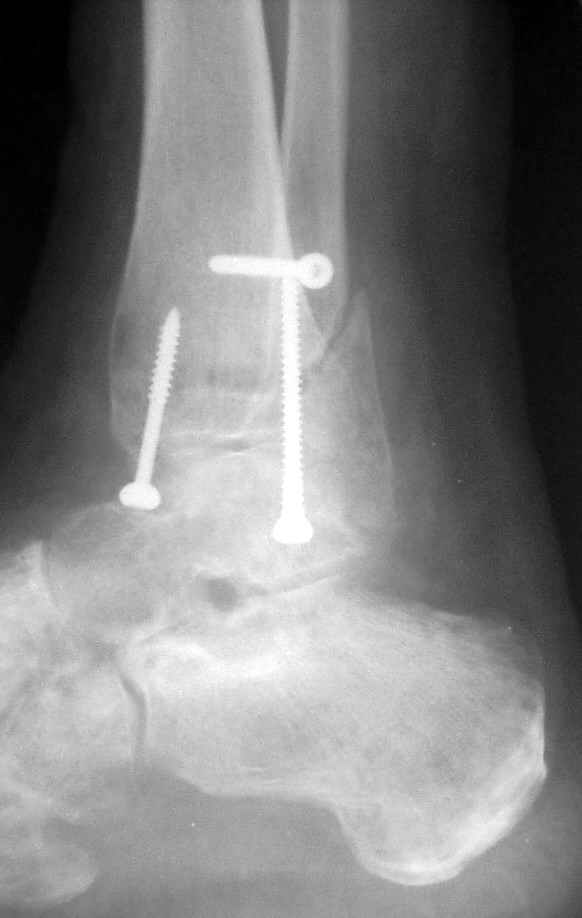

Операция 29 июля

Очевидно, такой результат операции был запрограммирован. При невосстановленной длине и практически нефиксированной малоберцовой кости (этот кортикальный винт - как карандаш в стакане), при неустраненном подвывихе, невправленной и тоже нефиксированной внутренней лодыжке нет стабильной вилки сустава. Если такую операцию сделать даже сразу, а не через 4 месяца, то результат ожидаем

тот же.

Ну а уж если выбран остеосинтез - нначать надо было с репозиции малоберцовой кости с точным восстановлением длины, с фиксацией треть-трубчатой пластиной по задней поверхности. Позиционный винт

избыточен - повреждение практически подсиндесмозное. А если бы

действительно было повреждение синдесмоза - в 4 месяца позиционный винт - не решение. Внутренню лодыжку такую - надо было бы спицами и проволочной петлей. Извините за эти банальности.

Вариант с артродезом уже обсудили. Хотя, после увиденых снимков, пессимизм насчет восстановительной операции у меня, например, несколько уменьшился. Особенного уж какого-то остеопороза не видно даже на январских снимках. Можно черед мини-доступы убрать винты, аппаратом вправить малоберцовую кость, устранить подвывих стопы. Ну а дальше фиксировать малоберцовую пластиной сзади. А может, и напряженной Y-спицей попробовать - Анатолий Федорович, как Вы полагаете? Внутреннюю - то, что осталось, если уже не получится сделать спицами и проволокой, то что-то типа пластики дельтовидной связки. А может, и не трогать ее вовсе... В общем, выбор непростой,

много факторов надо взвесить.